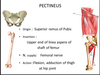

pectineus